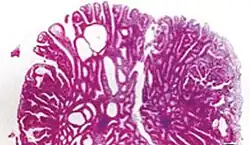

| Tubular adenoma | 2% at 1.5 cm[12] | Low to high grade dysplasia[13] | Over 75% of volume has tubular appearance.[14] |

|

Micrograph of a tubular adenoma, the most common type of dysplastic polyp in the colon -

-